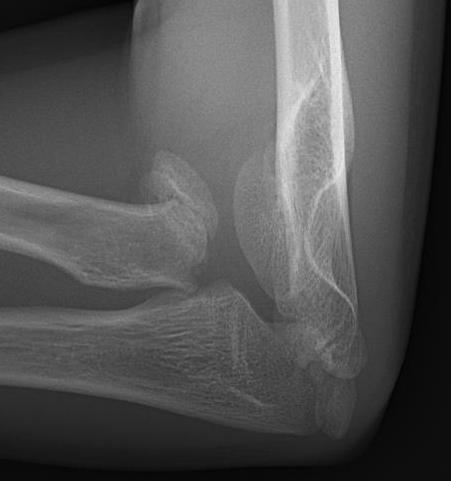

Xray

Displaced and angulated radial neck fracture